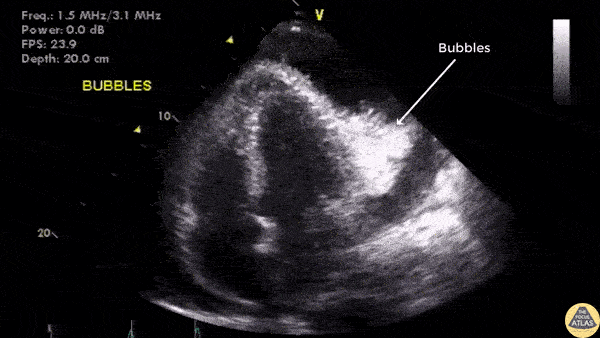

Pericardial Disease - Confirmation of Needle Placement For Pericardiocentesis

Initial stage of the pericardiocentesis. Agitated saline was injected to confirm needle location prior to withdrawing bloody fluid. Image courtesy of Robert Jones DO, FACEP @RJonesSonoEM Director, Emergency Ultrasound; MetroHealth Medical Center; Professor, Case Western Reserve Medical School, Cleveland, OH View his original post here